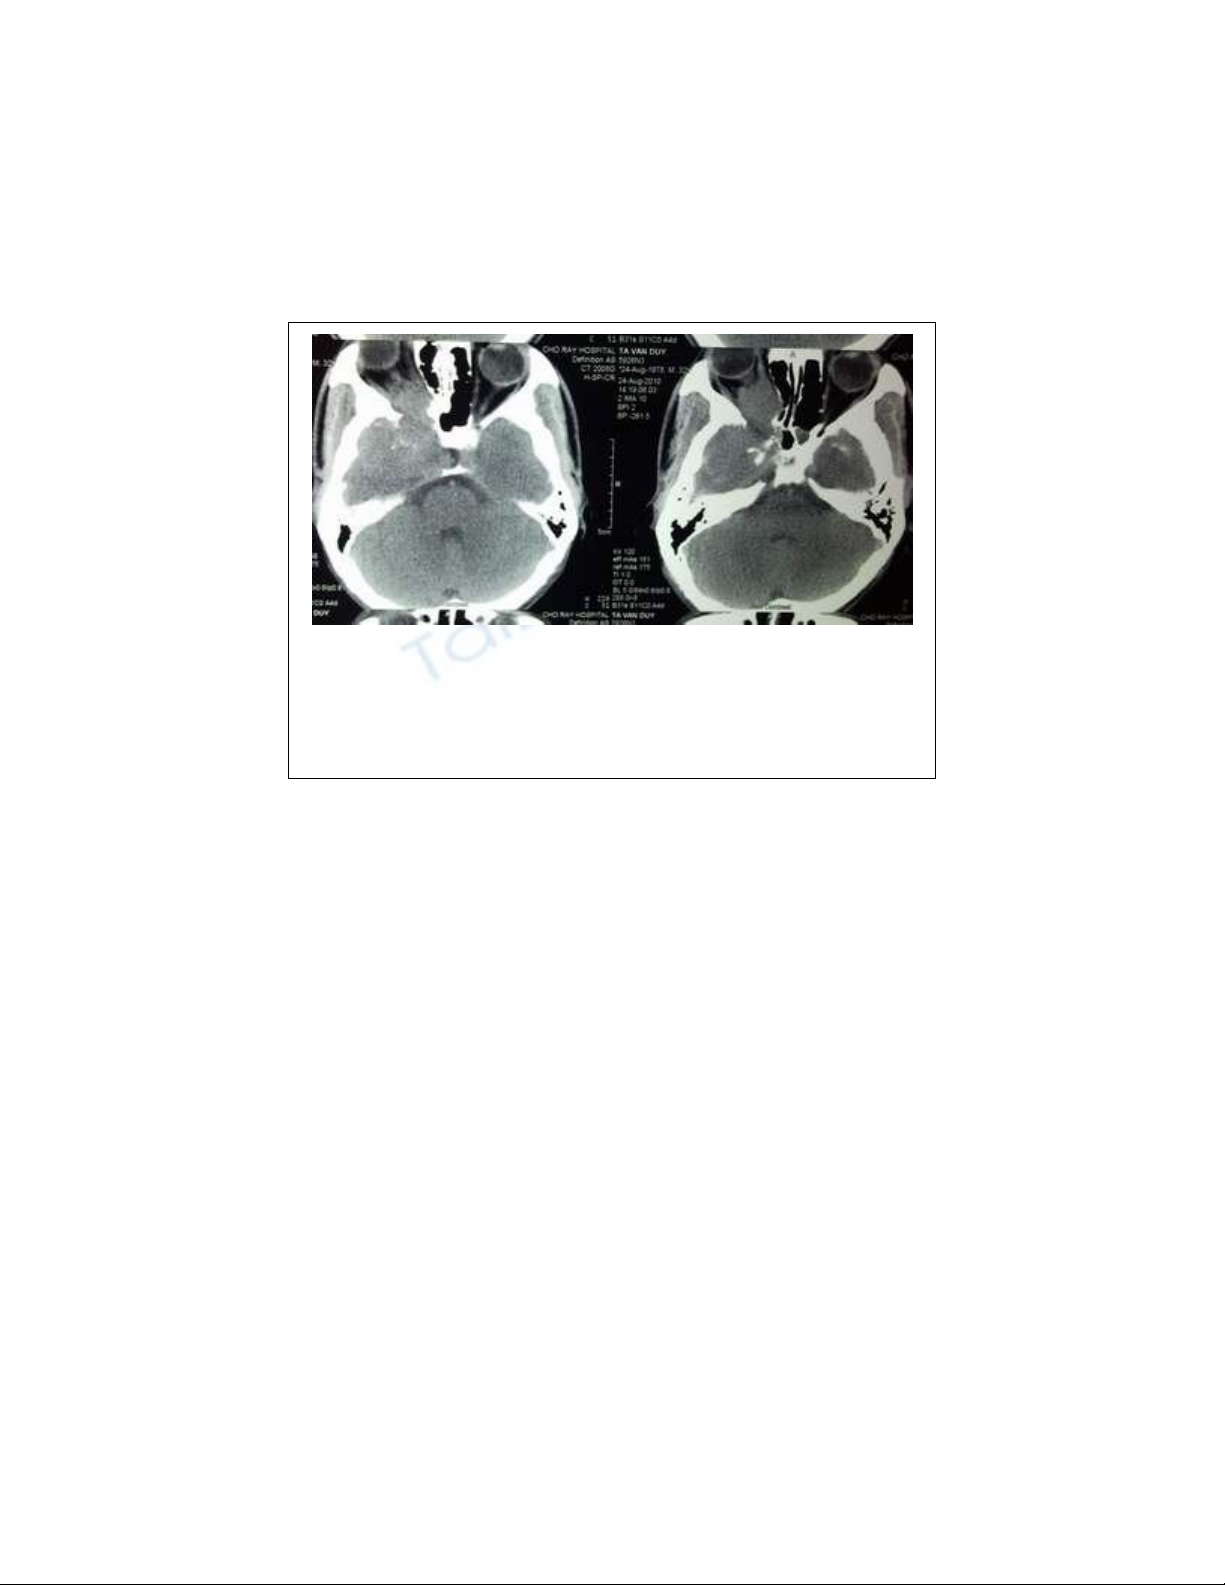

Hình ảnh khối u vòm xâm lấn sọ trên phim chụp

MRI.

Chẩn đoán xác định được thực hiện qua thăm khám lâm sàng: Khối

u màu hồng, xuất hiện ở cửa mũi sau của bệnh nhân nam giới tuổi

từ 15-25, có chảy máu mũi từng đợt, chụp CT. Scanner và chụp

mạch để có chẩn đoán xác định.